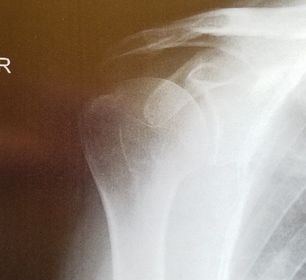

| AP Shoulder internal rotation | the MCP is tilted posteriorly as marked by the superior scapular angle is inferior to the clavicle |

| AP Shoulder | patient is rotated towards the unaffected shoulder: decreased thoracic superimposition over the scapular body |

| AP Shoulder | patient is rotated towards affected side:increased thoracic superimposition over the scapular body |

| AP Shoulder Neutral | ANATOMY: proximal humerus, lateral 2/3 of clavicle, open shoulder joint CRITERIA: humeral epicondyles are 45 degrees to the IR neither tubercle should be seen on the humeral head POSITIONING: CR perpendicular @ 1'' inferior to coracoid process |

| AP Shoulder Internal Rotation | CRITERIA: lesser tubercle in profile medially POSITIONING: CR perpendicular @ 1'' inferior to coracoid process |

| AP Shoulder External Rotation | CRITERIA: greater tubercle in profile laterally POSITIONING: CR perpendicular @ 1'' inferior to coracoid process |